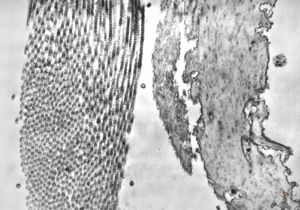

F,44y. | striations of fibrin - heart atrium, myxoma

M,28y. | striations of fibrin - aortal valve, endocarditis